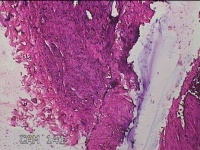

左侧手背结节

性别

男

年龄

43岁

临床诊断

皮下结节

一般病史

患者于近1个月来发现左侧手背一结节,伴局部隐痛不适,无发热。

标本名称

大体所见

灰白暗红色结节1.2x0.3x0.2cm一个,表面光滑。

疑似 :血栓形成。